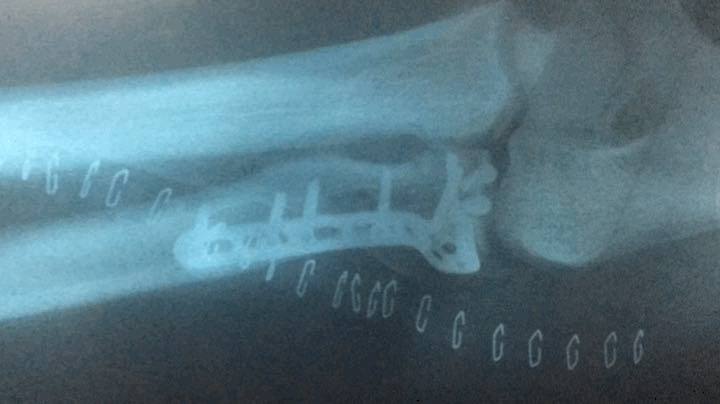

Nine steel nails and a steel plate were implanted in Yang Du's body after surgery. The dense needle feet were covered with elbows and ankles ... The doctor said that if the recovery is not good, it may face the worst results. It's "disability" ...